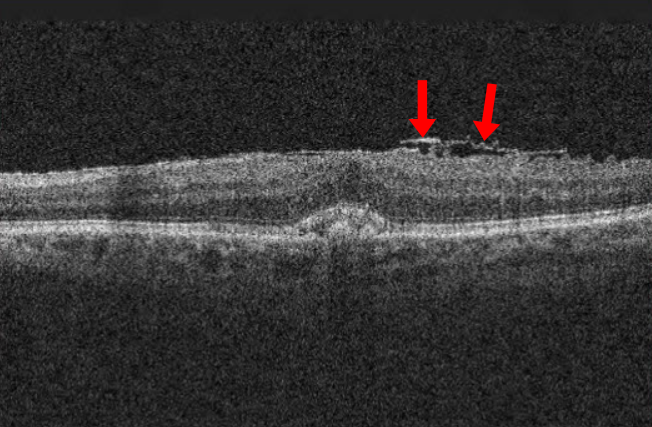

연세의대 안과 연구팀이 국제학술지 '망막'(Retina) 최근호에 발표한 논문에 따르면, 2017∼2020년 국민건강영양조사(KNHANES)에 참여한 1만5천240명을 분석한 결과 평일 평균 수면시간이 6시간 미만인 사람은 그렇지 않은 사람보다 망막전막 발생 위험이 25% 높은 연관성이 관찰됐다. 망막전막은 우리 눈에서 빛을 감지하고 뇌로 신호를 전달해 시력을 유지하는 핵심 부위인 망막의 앞 표면에 반투명한 막조직이 형성되면서 황반 기능에 이상을 일으키는 질환이다. 망막앞막, 황반주름 등으로도 불린다. 초기에는 뚜렷한 자각 증상이 없고 50세 이상 중장년층에서 발병률이 높아 노안으로 오인하기 쉽지만, 질환이 진행하면 물체가 휘어져 보이거나 상이 찌그러져 보이는 변시증, 시력 저하 등이 나타나고 결국에는 그 기능을 상실할 수도 있다. 연구팀은 이번 연구에서 망막전막 발생에 영향을 미치는 주요 변수로 나이(노화), 백내장 수술력, 이상지질혈증, 수면 부족 등을 꼽았다. 이 중에서도 수면 부족은 조절할 수 있는 위험 요인이라는 점에서 평소 일상생활에서 주의해야 한다는 게 연구팀의 분석이다. 연구팀은 수면 부족이 이어지면 망막 표면에서 활성화되는 여러 세포의 섬유화가 촉진됨으로써 결국 불필요한 막 조직이 만들어질 수 있는 위험이 커진다고 봤다. 실제로 만성적인 수면 부족은 전신의 염증 상태를 유발하고 면역 조절 기능을 약화하며, 혈관 항상성을 무너뜨려 심혈관질환이나 대사질환을 일으키는 것으로 알려져 있다. 여기에 노폐물을 제거하는 기능까지 떨어지면 유리체와 망막 사이 공간에 염증 매개물과 성장인자(TGF-β1)가 축적되고, 이에 따라 망막 세포들이 섬유화 반응을 일으킬 가능성이 높아진다는 게 연구팀의 설명이다. 이번 연구에서는 당뇨병 환자에게서 수면 부족과 망막전막의 연관성이 더 뚜렷했다. 당뇨병 자체가 미세혈관 염증과 망막 손상을 유발하는 만큼 수면 부족이라는 추가 요인이 더해지면 망막 환경이 더욱 취약해질 수 있다는 의미다. 망막전막은 진행 속도가 비교적 느려 일상생활에 큰 불편이 없으면 경과 관찰을 하기도 한다. 보통은 충혈과 통증 없이 시력의 변화만 나타나기 때문에 눈을 한 쪽씩 가리며 스스로 '암슬러 격자' 검사를 해봐야 한다. 이때 선이 휘어지거나 끊어져 보이는 등 시력 저하가 뚜렷하다면 안과에서 망막 검사, 빛간섭단층촬영 등을 통해 질환 여부를 확인하는 게 바람직하다. 만약 막이 심하게 달라붙어 망막 변형과 시력 저하가 심해지면 눈 속 유리체를 제거하고 섬유성 막을 직접 제거하는 유리체절제술이 필요하다. 다만 수술 후에도 변형된 망막 구조가 완전히 정상으로 회복되지 않는 경우가 많아 조기 발견과 예방이 무엇보다 중요하다. 김안과병원 망막병원 유영주 전문의는 "노년층의 망막전막은 발병률이 높지만, 초기에 자각할 수 있는 증상이 없거나 미미한 게 특징"이라며 "정기적인 안과 검진을 통해 본인의 눈 상태를 체크하고 적절하게 조치하는 게 노년기 눈 건강을 지키는 첫걸음"이라고 말했다.